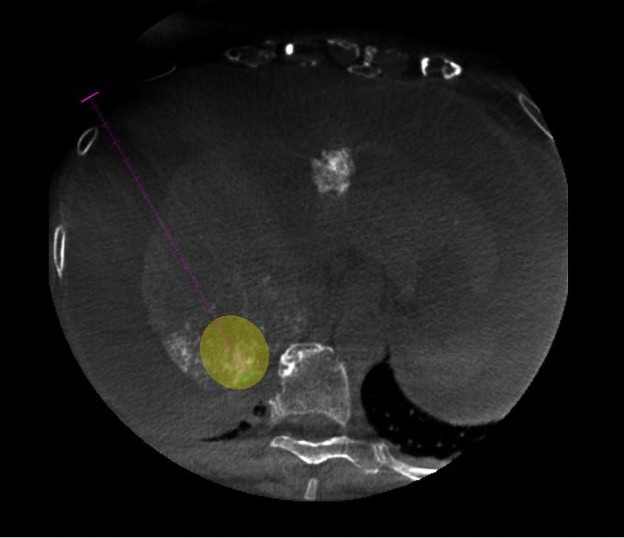

Equipped with sophisticated advanced image-guidance systems and multi-imaging modalities, our physicians may now better visualize and treat patients with complicated diseases. This system includes technology to make this easier in both 2D and 3D with dose reduction technology. It is equipped with integrated Intravascular Ultrasound. Vessel Navigation guidance, 2D Vessel Perfusion, 3D roadmap and Vessel quantitative measurements are offered as well. Vessel Navigator allows reuse of 3D vascular anatomical information from existing CTA and MRA datasets as a 3D roadmap overlay on live X-ray images. With its sophisticated visualization, it provides an intuitive and continuous 3D roadmap to guide you through vasculature during the entire procedure. The system is connected to our PACS system allowing us to visualize previous diagnostic images inside the room.

As the clinician moves the system, the image beam automatically maintains alignment with the patient, allowing more consistent visualization and enabling them to keep their focus on the treatment. In addition, the room has ability to perform cone-beam XperCT, which will allow us to move some interventional procedures from one of the CT scanners on the first floor of University, further freeing-up capacity for diagnostic CT.